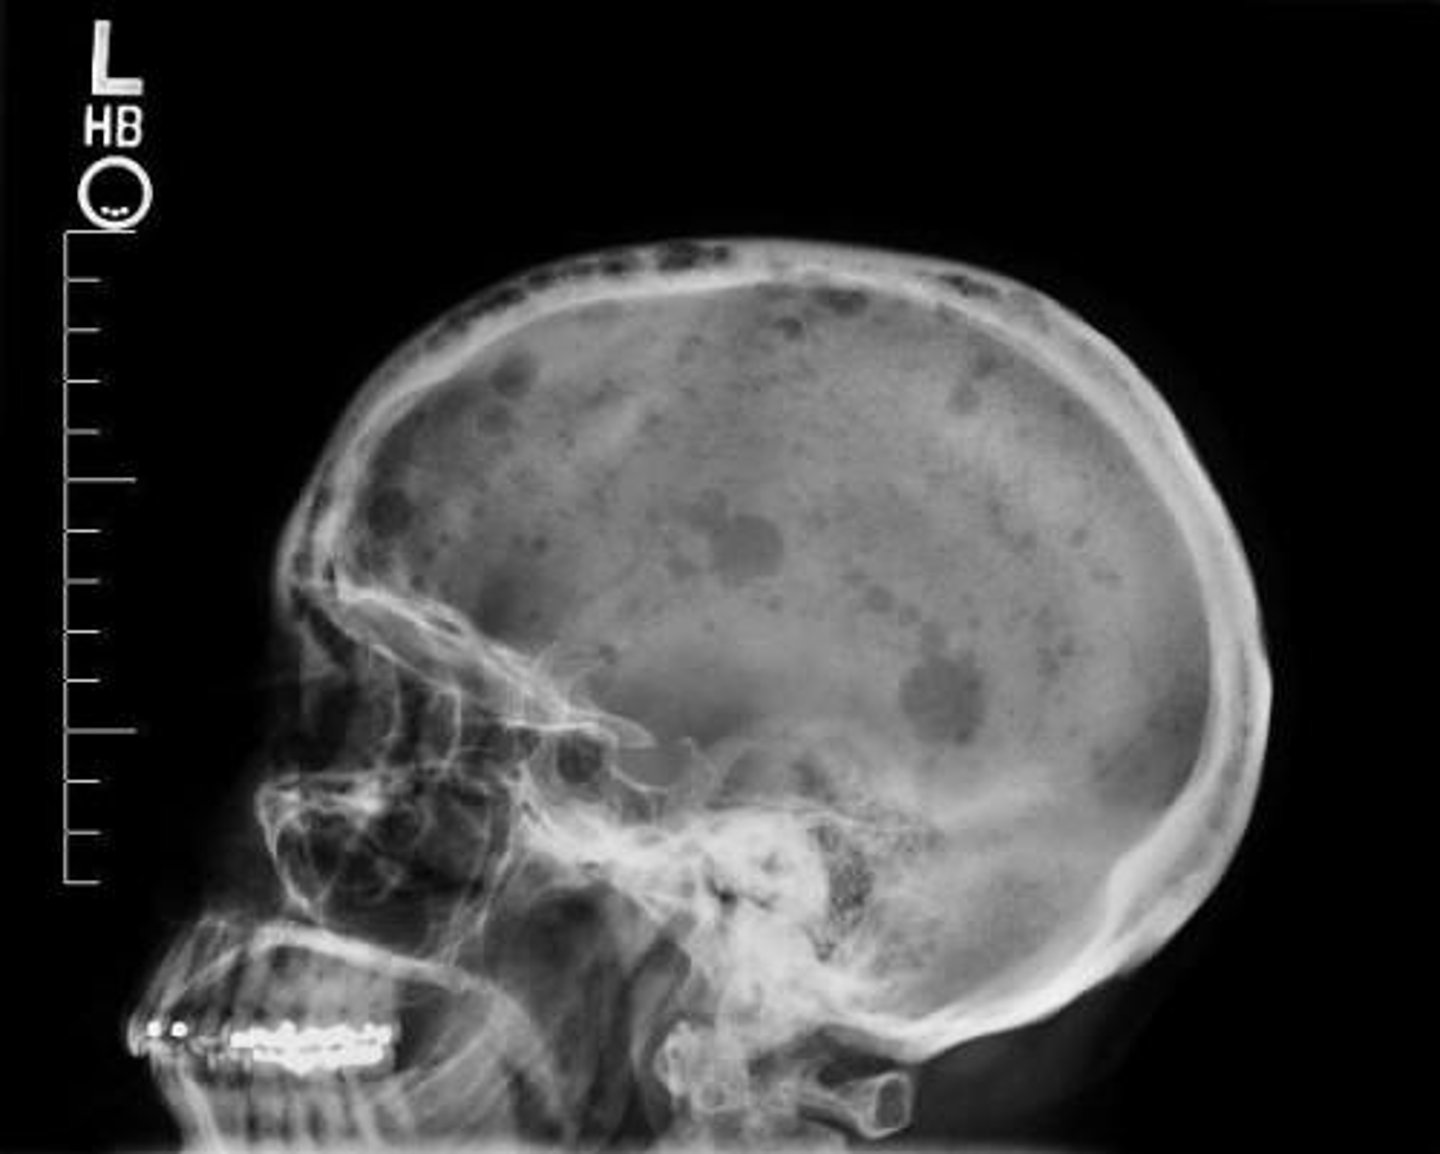

•Bone fractures, due to calcium leaching from bones into circulation. Punched out lesions on X ray.

<p>•Fatigue, due to anemia</p><p>•Excessive thirst/urination, due to excess calcium</p><p>•Nausea, due to excess calcium</p><p>•Bone pain/back and ribs, due to plasma cell acceleration</p><p>•Bone fractures, due to calcium leaching from bones into circulation. Punched out lesions on X ray.</p><p>•Unexpected infections, due to compromised immunity</p><p>•Weakness and numbness in the legs, due to vertebrae compression.</p>